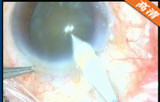

2.2mm微切口白内障超声乳化+人工晶体植入手术

该手术做2.2mm角巩膜缘主切口及侧切口; 前房注入医用透明质酸钠; 连续环形撕囊; 水分离、水分层;超声乳化核和核壳 ,注吸皮质; 抛光前囊和后囊; 前房及囊袋内注入透明质酸钠凝胶; 植入折叠人工晶体; 吸除透明质酸钠凝胶; 水密切口。

关键词: 2.2mm微切口 白内障 超声乳化 折叠人工晶体